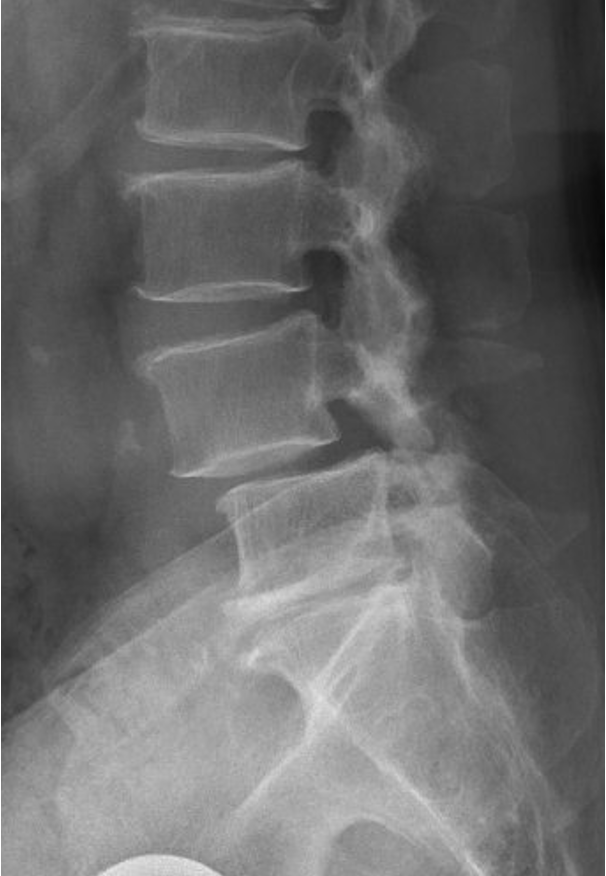

X-ray image of a human lumbar spine showing vertebrae and intervertebral discs.

When Is Posterior Lumbar Fusion Recommended?

This procedure may be recommended when both nerve compression and spinal instability are present.

Common conditions include:

• Lumbar spinal stenosis with instability

• Lumbar spondylolisthesis

• Degenerative changes causing nerve compression

• Recurrent disc herniation with instability

Fusion is often recommended when decompression alone would leave the spine unstable.